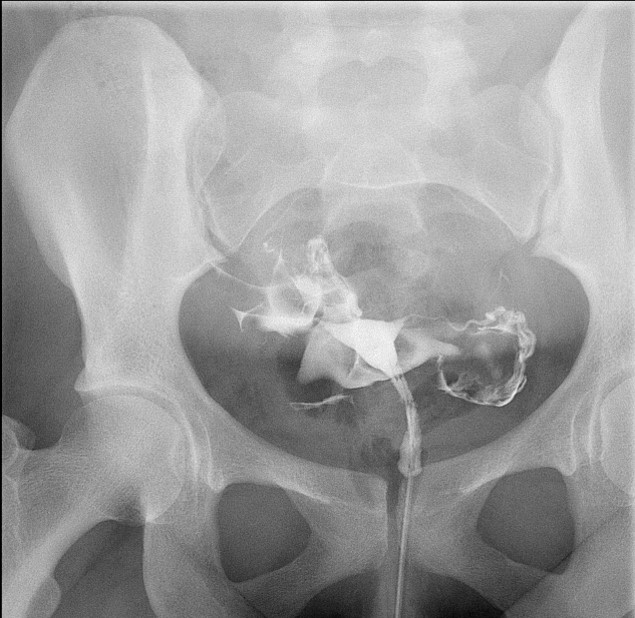

- When reviewing the preliminary scout film, you should see multiple surgical chain sutures in the pelvis

(key image 31)

(key image 32).

- As you instill contrast material into the J pouch, obtain images of the pouch and ileoanal anastomosis fully distended with contrast material in each of the following four (4) positions:

- left lateral

(key image 34)

- left posterior oblique

(key image 35)

- supine (AP)

(key image 36)

- right posterior oblique

(key image 37).